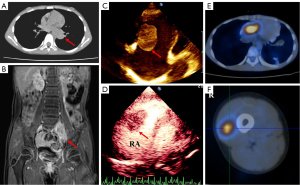

Three days prior to admission to our hospital, the patient developed a fever, and his temperature was 38.3–38.8 ℃. A review of the chest CT (September 17, 2019) showed diffuse multimorbidity in bilateral lungs, with rapidly progressing lesions, which were considered diffuse alveolar hemorrhage with vasculitis. Thrombosis in the right atrial was possible. In order to seek further diagnosis and treatment, he was transferred to the First Affiliated Hospital of Guangzhou Medical University (September 18, 2019). His vital signs at admission were as follows: temperature, 36.9 ℃; heart rate, 123 bpm; breath, 23 bpm; blood pressure, 114/60 mmHg; oxygen saturation (SPO2), 81%; and bilateral lower lung auscultation with crackles. The white blood cell (WBC) count was 10.5×109/L, the C-reactive protein (CRP) level was 2.14 mg/dL, and his hemoglobin (Hb) level was 50 g/L. The results of chest enhancement CT and 3-dimensional reconstruction (September 19, 2019) showed multiple polymorphic lesions in bilateral lungs, suggestive of vasculitic lesions or hematogenous lung infection may be possible, and alveolar hemorrhage in bilateral lungs (Figure 1A). The patient also had a right atrial filling defect (vegetation or thrombosis) and multiple slightly low-density nodules in the liver suggestive of hematogenous intrahepatic infection. Based on the results of relevant examinations, the possibility of a hematogenous disseminated lung abscess was considered. Vancomycin and meropenem were administered to counter the infection, and voriconazole was administered for antifungal treatment. The liver ultrasound and contrast ultrasonography (September 20, 2019) showed that intrahepatic lesions were benign (infectious lesions may be possible). The transthoracic echocardiography (TTE; September 19, 2019) review revealed an enlargement of vegetation on the tricuspid valve (Figure 1B) and a new neoplasm at the entrance to the inferior vena cava (Figure 1C). Transesophageal echocardiography (TEE; September 24, 2019) further found vegetation to the right auricle without adhesion to the tricuspid valve, with a size of 68 mm × 29 mm (Figure 1D). During hospitalization, multiple bacterial and fungal blood cultures were negative.

During a week of antifungal and antibacterial treatment, the patient’s symptoms did not improve significantly. Multiple infectious lesions in the lung and liver were thought to be caused by hematogenous disseminated infections that originated from macrovegetations in the heart. In the absence of an effective means to control the infection, after consultation and evaluation of cardiac surgeons, it was considered that the vegetation in the heart could be removed surgically to improve the infection and bleeding in the lungs. After thorough preparation, the surgery was performed on September 27, 2019. During the operation, a tumor was found in the right atrium, about 60 mm ×50 mm in size, which had invaded the atrial tissue. The mass was completely removed by the surgeon (Figure 2A). After surgery, endotracheal intubation and assisted ventilation were implemented, antifungal drugs were discontinued, and anti-infective therapy continued with vancomycin and meropenem. The patient’s vital signs were stable and SPO2 was 100%, but multiple bedside chest radiographs showed no significant changes in the bilateral lungs.

Two months later, the girl returned to our hospital. She had developed intermittent left leg pain and a cough for about 1 month, accompanied by hemoptysis for 5 days. Routine TTE showed a solid mass in the right atrium (27 mm × 22 mm) that had high mobility and was lobulated, and it was considered a malignant lesion (Figure 3C). The CT review suggested pleural metastasis in the right lower lung, so an ultrasound-guided biopsy with a 20-G biopsy gun (BARD® MAGNUM®) was performed on the pleura. However, the pathological finding was also infectious disease. To explore the nature of the atrial mass, further contrast echocardiography (CE) was performed, revealing a very rich blood supply within the mass. The perfusion intensity and time were similar to those of the myocardium, and there was no necrosis. The mass was diagnosed as a malignant tumor (Figure 3D). Then, positron emission tomography (PET)-CT was used to determine whether there were metastases throughout the body, and clear positive results were obtained. The right atrial mass was a primary cardiac malignancy (Figure 3E), and there was a metastasis between the muscles of the right middle thigh (Figure 3F). Ultrasound-guided biopsy with a 20-G biopsy gun (BARD® MAGNUM®) for the mass in the right thigh was performed, and the pathological result was Ewing sarcoma (Figure 4A-4D). A vindesine, ifosfamide, doxorubicin, and etoposide (VIDE) chemotherapy regimen was then used for the patient.

After 2 rounds of chemotherapy, the cardiac tumor was significantly smaller than before, pulmonary lesions had reduced significantly, and the mass in the right thigh had disappeared (Table 1). After the fifth round of chemotherapy, PET-CT showed no hypermetabolic tissue in the right thigh or right atrium (Figure 5A,5B). TTE still detected abnormal masses near the right atrial appendage, and the size was stable (Figure 5C). After 6 rounds of VIDE chemotherapy, the regimen was changed to vincristine, irinotecan, and temozolomide (VIT) chemotherapy, but no obvious changes were detected in TEE and PET-CT over the next 6 VIT chemotherapy sessions. Then, the girl stopped the chemotherapy and was followed up by TTE. About half a year later, TTE showed no obvious change in the size of the right atrial mass, but a new cord-like attachment was identified on the mass surface, which wiggled with the heartbeat (Figure 5D). The cord-like attachment did not increase or disappear during the follow-up, and its nature remained unclear.